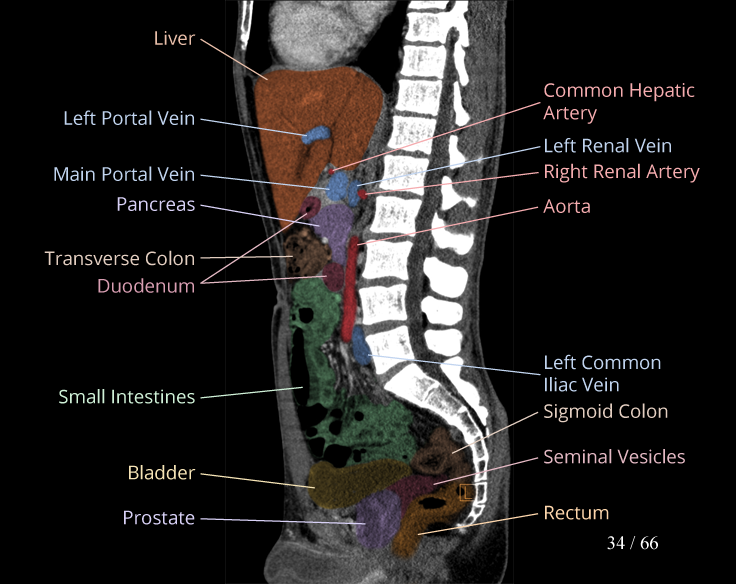

Body

Covers abdominal CT anatomy.